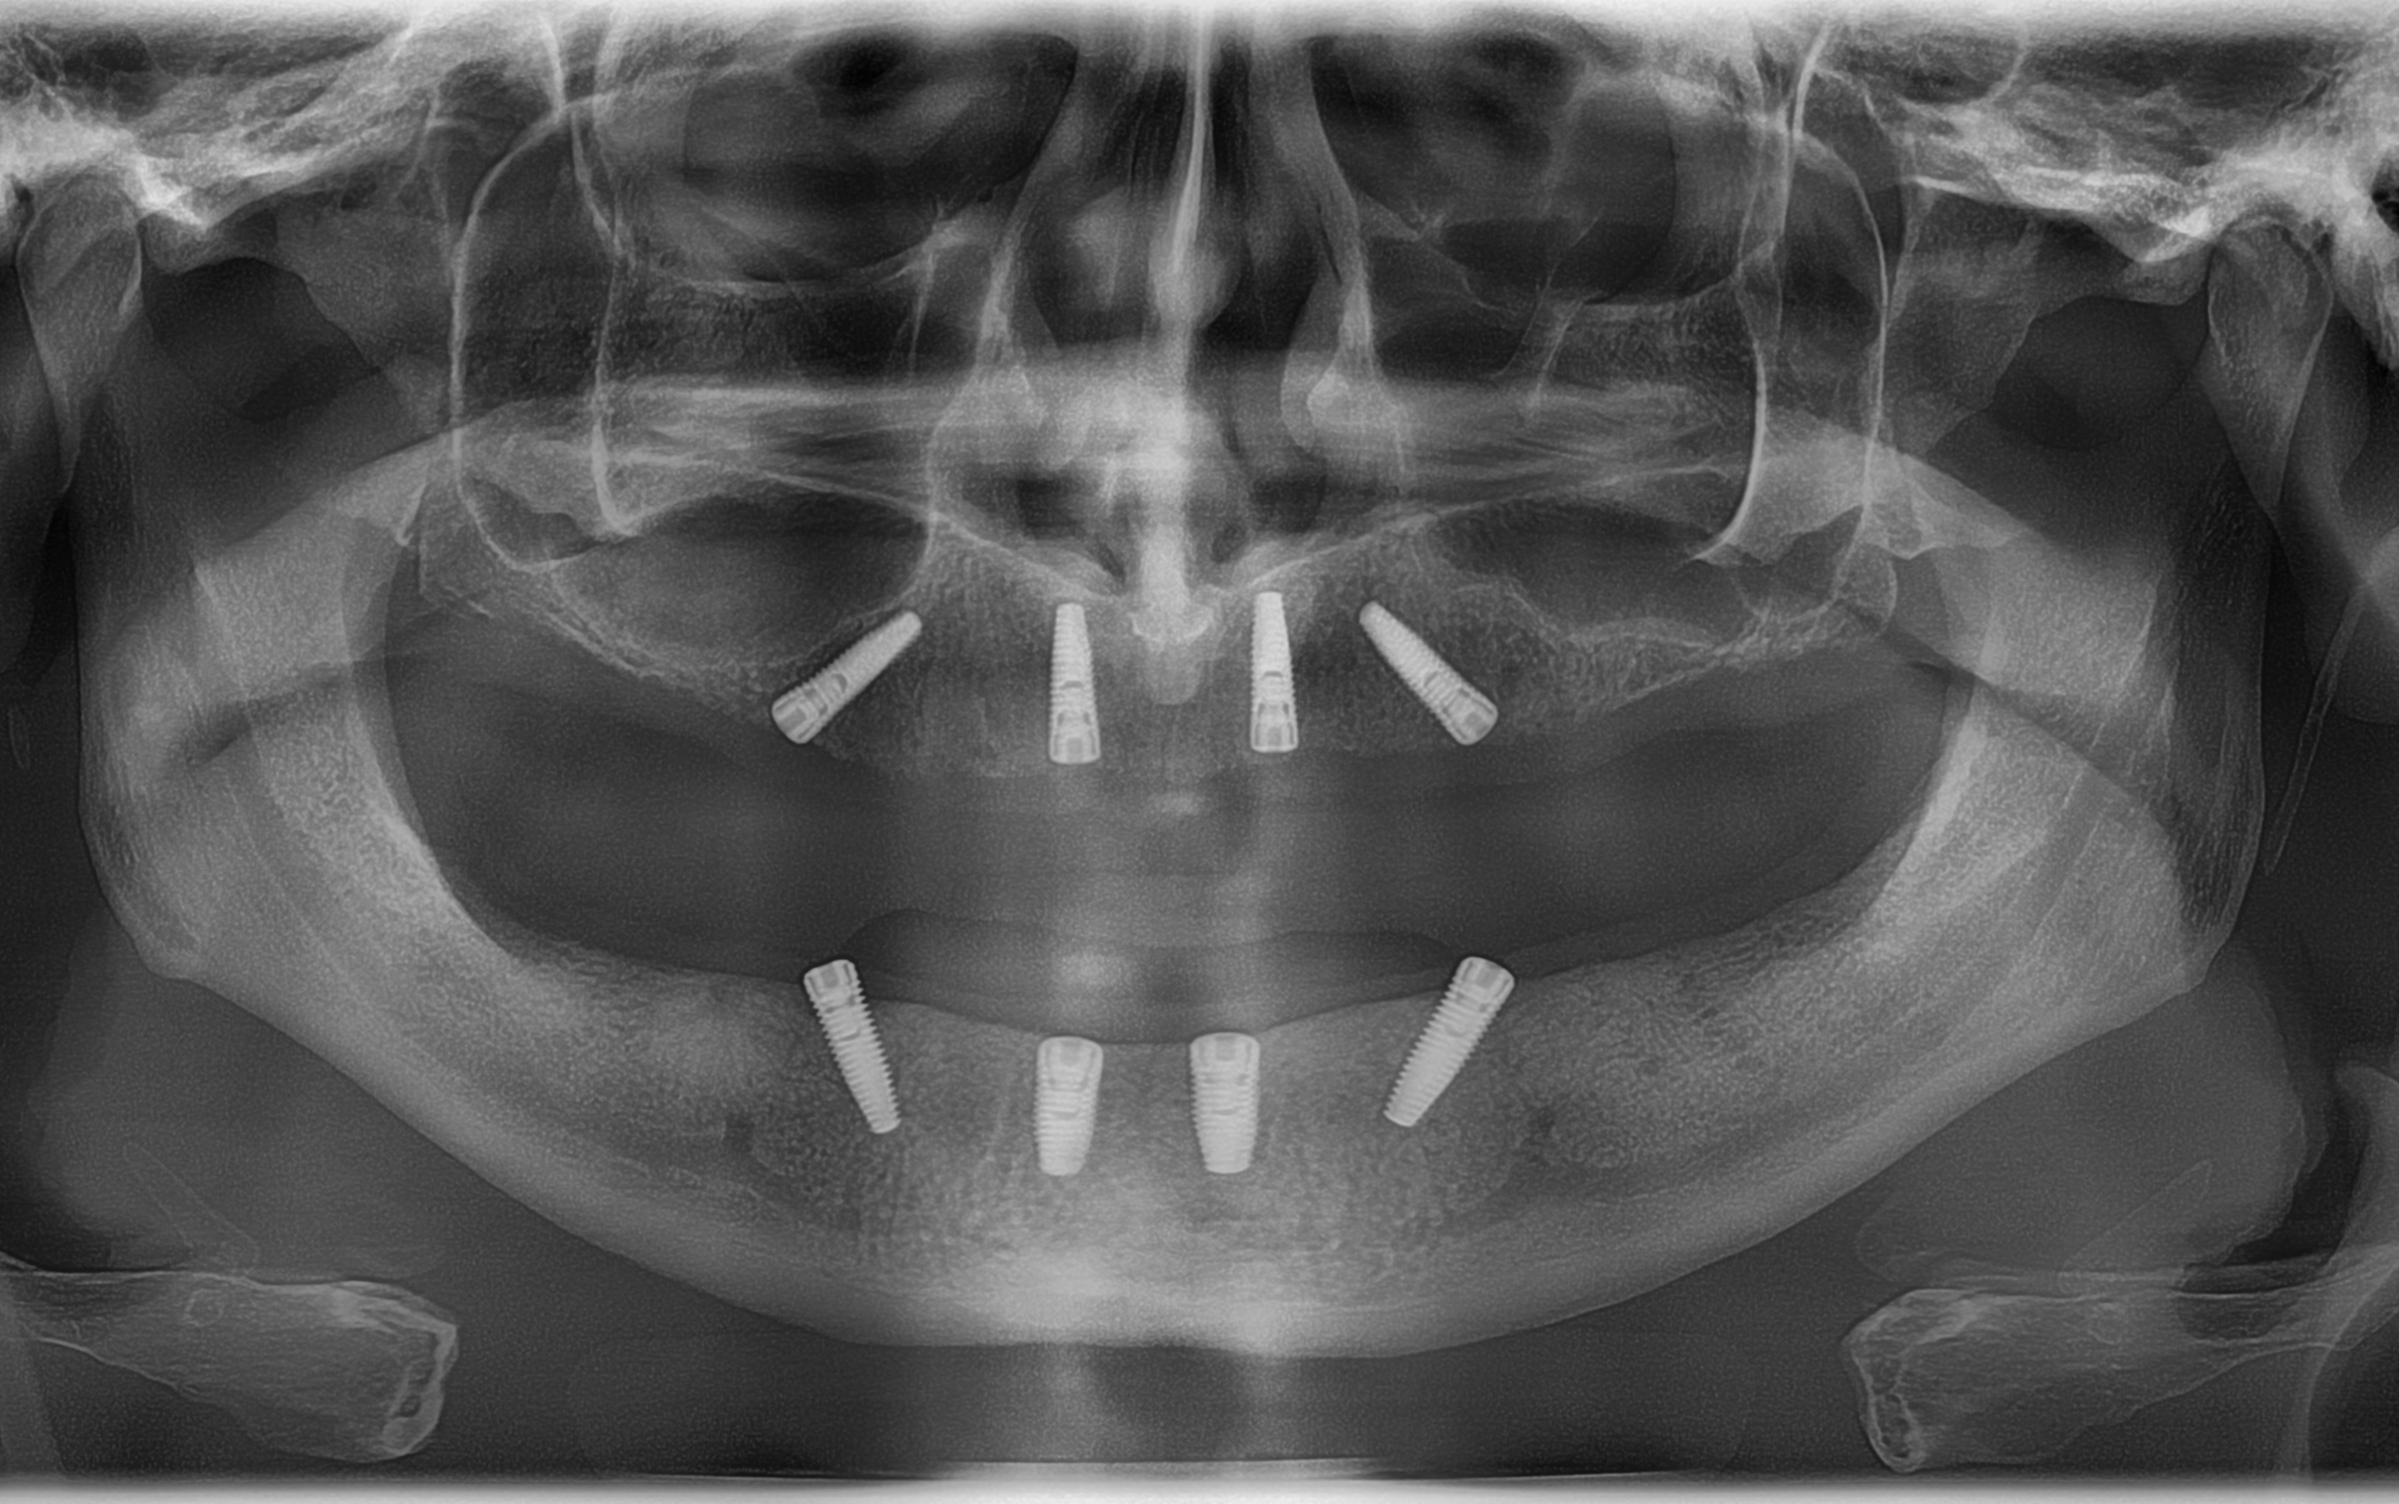

Brückenversorgungen auf 8 bereits vorhandene Implantate

• mit Auswechseln der Sekundärteile

• Implantate bereits vorhanden: 15, 12, 22, 25, 45, 42, 32, 35

• Implantathersteller: Oxy-Implantat PSK

• Implantate wurden gesetzt: Sept. 2023

Ich benötige 2 Brücken mit jeweils 12 Zähnen, die auf bereits vorhandenen 8 Implantaten (4 im OK und 4 im UK) verschraubt werden sollen. Material: PMME o.ä.